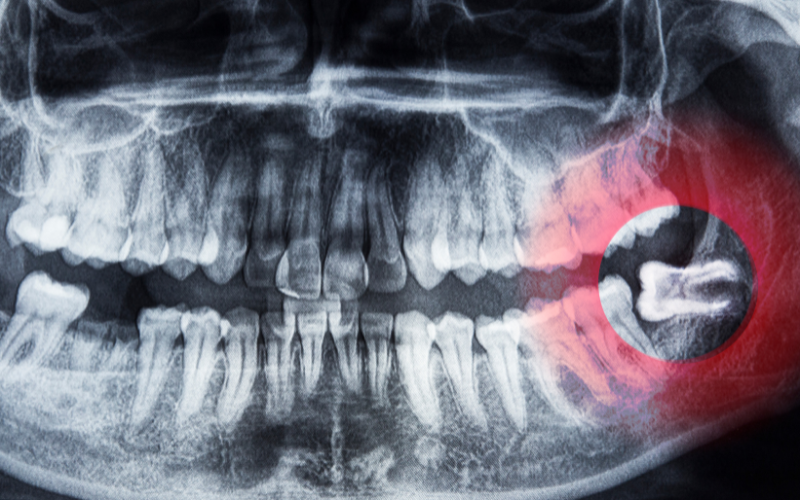

Impacted Wisdom Teeth – Teeth stuck under the gums or growing at an angle.

1️⃣ Consultation & X-ray – Evaluating tooth position and extraction necessity.